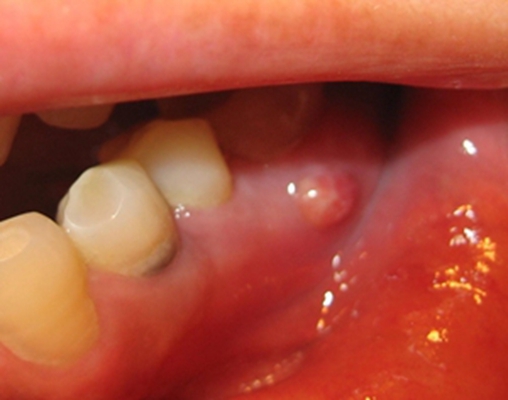

口腔癌圖片

口腔癌的前兆 (46)

口腔癌的前兆 (47)

口腔癌的前兆 (48)

口腔癌的前兆 (49)